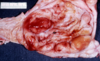

This is a stomach. What lesion is shown here?

gastric ulceration